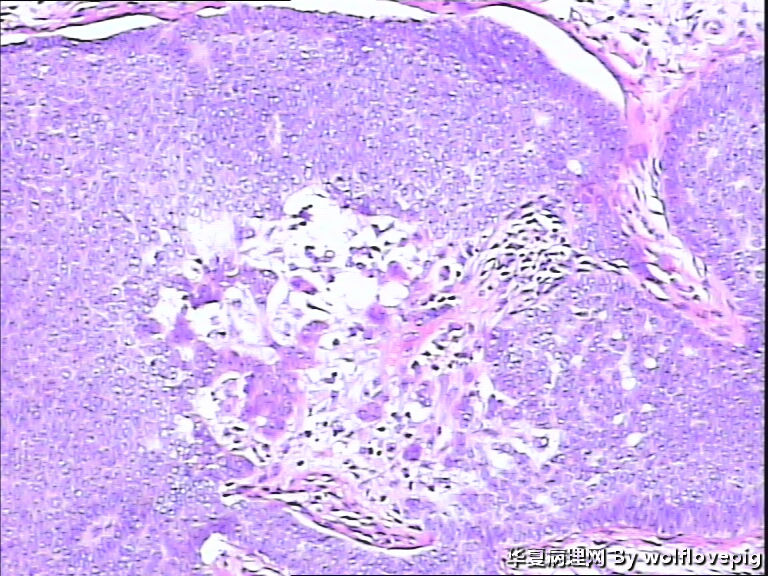

女,58y,右面部包块10年。灰白不整形带皮组织一块:2.3cm*1.5cm*0.3cm,切面有一灰白区域,质软,边界欠清。

诊断考虑毛母细胞瘤,或毛发上皮瘤。细胞团块周围可见嗜酸性纤维包绕,间质内纤维增生明显。

与表皮无关,表皮无破溃,无收缩间隙-------不支持BCC  有角囊肿 促纤维增生-----支持毛发上皮瘤

栅栏状外周结构,疏松的间质,基底细胞癌

诊断考虑毛母细胞瘤,或毛发上皮瘤。